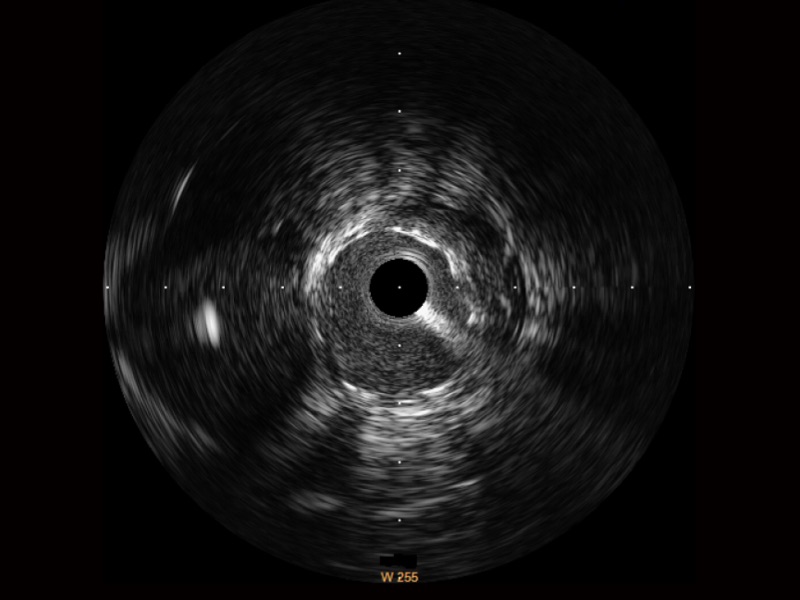

• 环球UG官网宽频IVUS图像

对比传统IVUS导管成像,环球UG官网宽频IVUS图像的近场支架梁显影更细腻,远场中膜外血管仍清晰可辨,兼顾远中近,兼顾分辨力与穿透深度